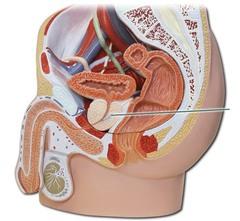

Bulbourethral gland (male)

Corpora cavernosa (pl.) Corpus Cavernosum (s.)

Corpus Spongiosum

Ejaculatory Duct

Epididymis

External urethral orifice (male)

Glans penis

Prostate gland

Prostatic/spongy urethra (males)

Scrotum

Seminal vesicle

Seminiferous tubule

Testis (s.) Testes (pl.)

Urinary Bladder (male)

Vas deferens (=ductus deferens)